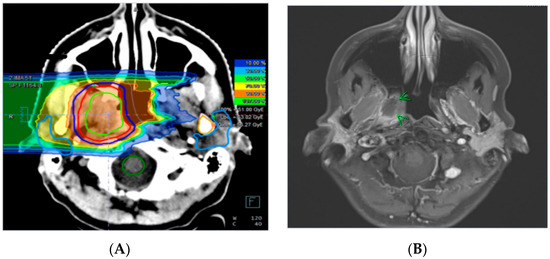

4.2. Treatment Planning and Radiotherapy

| Carbon ion re-irradiation (Gy (RBE)) | 51.0 | 39.0–60.0 |

| PTV re-irradiation (ccm) | 85.3 | 13.3–286.5 |

| Cumulative Dose (EQD2) | 133.9 | 112.5–152.3 |